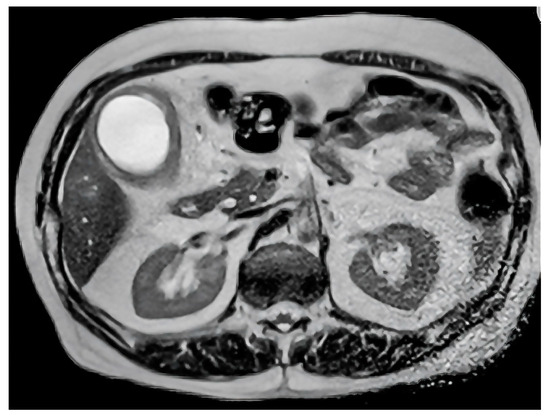

Figure 1.

Axial T2-weighted MRI scan demonstrating gallbladder wall thickening and intramural nodules, characteristic of xanthogranulomatous cholecystitis.